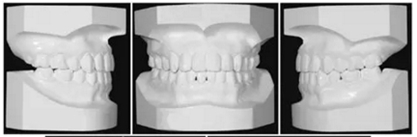

治療后面部和口內(nèi)照片顯示治療結(jié)果很成功(Figure 8)?;颊叩拿嫘瞳@得了非常顯著的改善,尤其是在唇部區(qū)域。覆合從-3.5mm增大到3.5mm,覆蓋從1.2mm增大到2.0mm。獲得了I類磨牙關(guān)系,沒有擁擠(Figures8 and 9)。

頭測顯示:下頜平面角從46.7°減小到44.0°。上頜第一磨牙高度減小1.2mm。面高有減小(N-Me: 133.2 mm to 127.7 mm, Ans-Me: 78.5 mm to 72.6 mm; Table 1,Figures 10B and 11)。上下頜切牙顯示腭側(cè)和舌側(cè)傾斜(U1-SN: 95.8°to 91.8°, IMPA: 83.7°to 77.7°)。

治療前后頭影疊加圖清楚地顯示,下頜發(fā)生逆時針旋轉(zhuǎn),上下切牙舌側(cè)移動(Figure 11)。CT顯示髁突未發(fā)生形態(tài)改變,而磁共振T2影像顯示有形態(tài)改善(未提供圖像)。在治療期間沒有出現(xiàn)顳下頜關(guān)節(jié)癥狀。

保持2年后,患者的面型和咬合關(guān)系獲得了良好的維持,并且患者對治療結(jié)果非常滿意(Table 1, Figure 12)。任一側(cè)都沒有出現(xiàn)顳下頜關(guān)節(jié)紊亂情況。